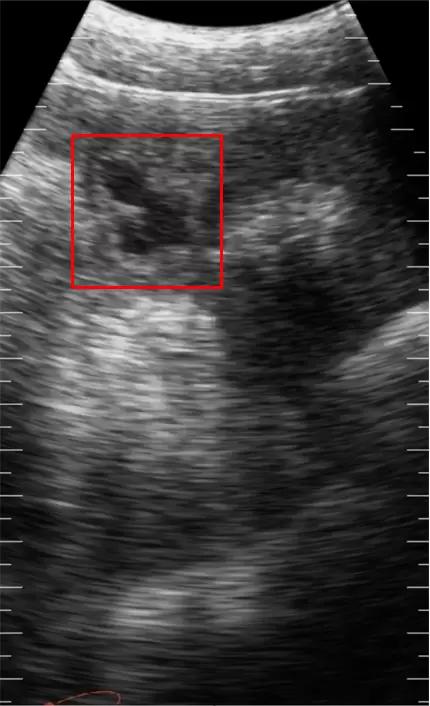

Черный - показывает нам полости с жидкостью, так как жидкость не отражает Ультразвук, такие области называются Анэхогенными.

А теперь на примере снимка молодой свинки на стадии созревания

Большая часть изображения серая, видны некоторые затемнения, структуры плохо различимы, так как свинка ещё молодая и не осемененная. Небольшой белый отблик - стенка матки.

Справа- черного цвета - это мочевой пузырь.